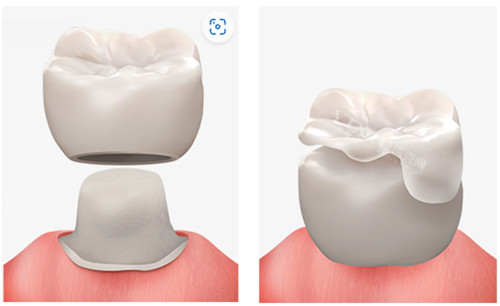

种植牙:如果牙槽骨条件允许,种植牙是较为理想的选择。它能较好地修养牙齿的功能和美观,咀嚼效率高,使用寿命长。种植牙是通过手术将人工牙根植入牙槽骨内,待牙根与牙槽骨紧密结合后,再安装牙冠。不过,种植牙对患者的身体状况和牙槽骨条件要求较高,手术过程相对复杂,费用也相对较高,一般在 8000 - 20000 元不等。

烤瓷牙或全瓷牙桥修复:当相邻牙齿健康且稳固时,可考虑烤瓷牙或全瓷牙桥修复。这种修复方式需要磨除相邻的健康牙齿作为基牙,然后制作连冠桥体来修复缺失牙。其优点是修复后的牙齿外观和功能较好,但缺点是会对相邻的健康牙齿造成一定损伤,且使用寿命相对种植牙较短。烤瓷牙价格大概在 1000 - 5000 元一颗,全瓷牙价格在 2000 - 8000 元一颗。